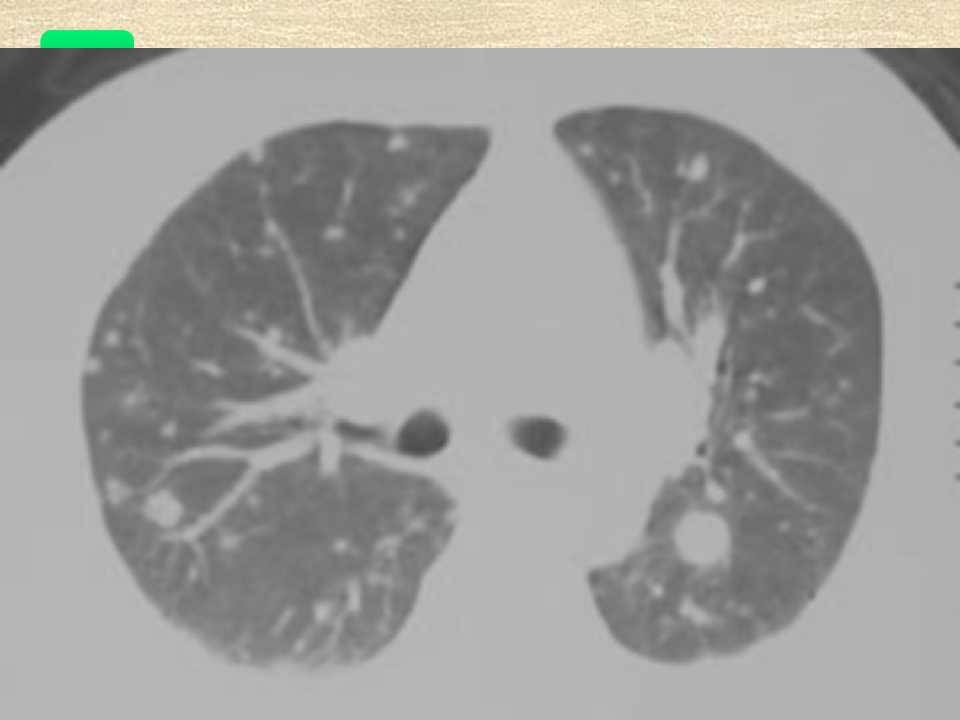

肺癌影像学表现